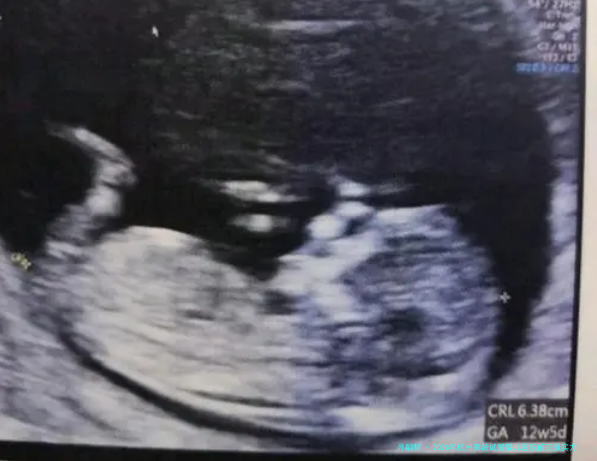

细致说明:浙大妇院生殖中心在中年女性助孕范围积累了大量的临床数据和研究经验。他们特别重视对卵巢储备功能的精细评估(如AMH、窦卵泡计数)和各别化促排卵方案的制定,擅长使用微刺激、黄体期促排等更适合高龄卵巢状态的方案,以在获取可用卵子和减少身体承当间找到平衡。其壮大的胚胎遗传学诊断与筛查技术,是帮助高龄夫妇获得健康宝宝的重要保障。

A: 核心是胚胎质量和子宫内部环形境。年龄主要影响卵子质量,导致染色体不同寻常率升高。三代试管技术(PGT)进行胚胎筛选尤其首要。良好的内膜容受性是胚胎着床的“泥土”,需提前排查宫腔问题。

1.全方位评介:进行AMH、性六项、窦卵泡计数等卵巢功能检查,以及宫腔镜、内膜活体组织检查等宫腔评价。

3.胚胎筛选:热烈建议进行胚胎移植前遗传学检查,筛选染色体正常的胚胎进行移植。